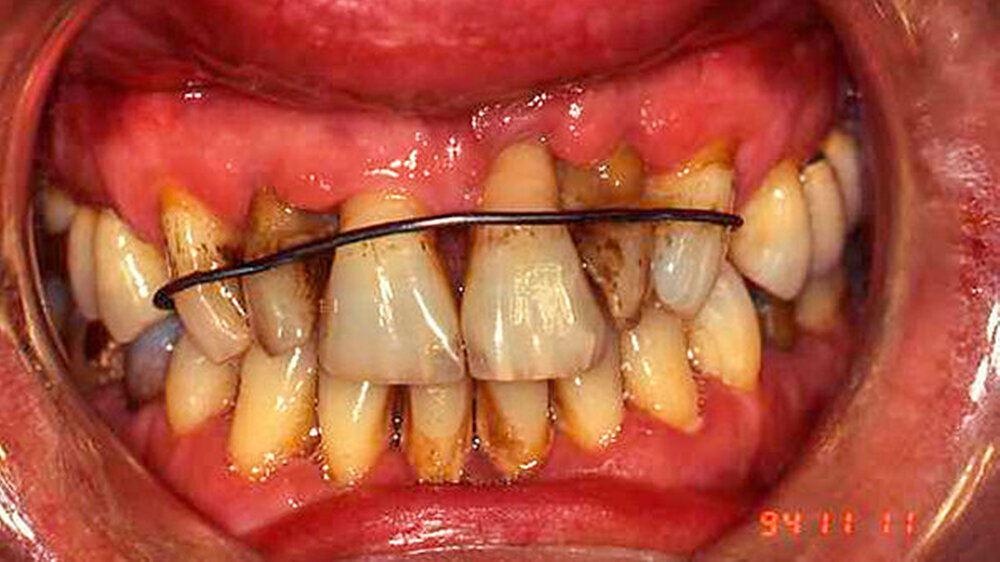

Festgezurrt mit Blumendraht

Dieser Fall wurde eingereicht von Dr. Wilfried Forschner, Köhlestrain 86, in 88400 Biberach

"Die Ausnahmefälle kommen Freitagabend kurz vor Praxisschluss", heißt es oft in Fortbildungen. Genauso ist es. Und wenn nicht, sind es Fälle, die auch nach der Arbeit im Gedächtnis bleiben.